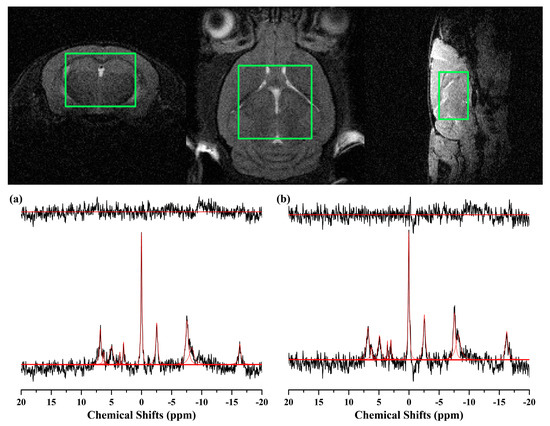

2.2. 1H MRS

2.3. 31P MRS